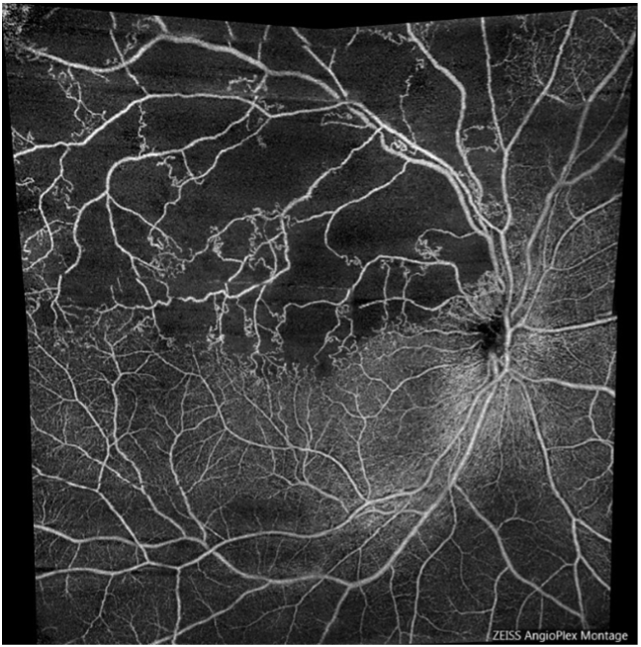

網膜静脈分枝閉塞症

また、この機種にはOCT Angiography(OCTA)という機能も備わっており、網膜血管の形状を高解像度で撮影することも可能です。

眼底の血管病変を調べるには、点滴から造影剤を静注する蛍光眼底造影検査という検査を行う必要があったために、アレルギー等の心配も懸念されました。OCTAを用いることで、造影剤を使わず安全に網膜の血管構造の取得が可能になりました。

糖尿病網膜症や網膜血管閉塞症、加齢黄斑変性症などの血管病変に対し、リスクを抑えながら頻回の検査を行うことができます。(蛍光眼底造影検査でのみ得られる所見もあります)